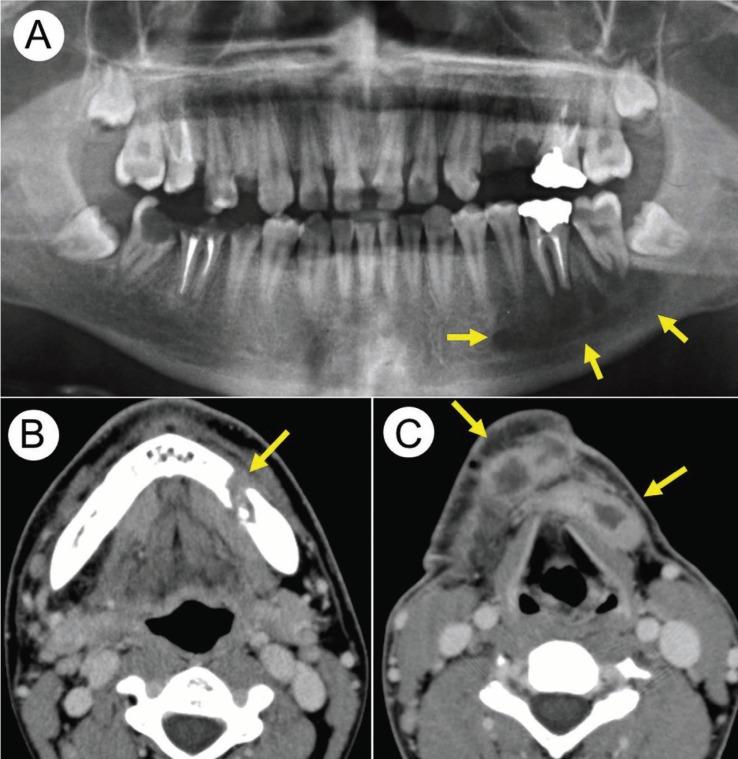

Hyperimmunoglobulin E syndrome is a primary immunodeficiency state that is characterized by eczema, recurrent skin and lung infections, and markedly increased levels of IgE. Odontogenic infection can spread to vital and deep structures in such immunocompromised patients. We report a case of a 19-year-old man with hyperimmunoglobulin E syndrome presenting deep neck space infection that had spread from periapical periodontitis of the lower molars. A computed tomography scan showed an area of bony destruction in the left mandible and abscess formation in the submandibular and submental spaces. The patient was successfully treated by cervical drainage, extraction of the causative teeth, and antibiotic therapy. The present case highlights the importance of adequate treatment of dental infections in immunocompromised patients. Hyperimmunoglobulin E syndrome, odontogenic infection.